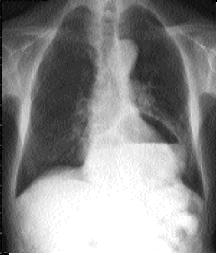

Hernie hiatale : Image

radiologique sans preparation , cliche pulmonaire de

face . Image hydro-aerique a gauche , en arriere le

bord gauche du coeur |